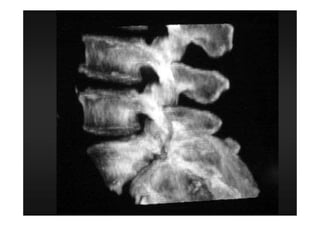

RADIOLOGIA DO

TRAUMA DO ESQUELETO

Referência: http://www.accessexcellence.org/RC/VL/